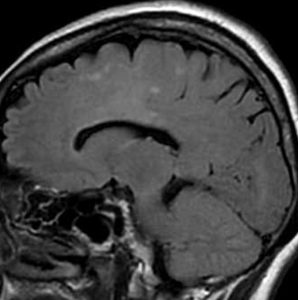

2001年に無症状で偶然発見された右辺縁回の限局性星細胞腫 well-deliniated or localized astrocytomaと呼ばれるものです。非常に限局性で,T2で強い高信号になりT2-FLAIR mismatch signがあり,T1では低信号でガドリニウム増強されない典型的画像です。